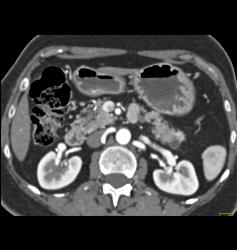

DIEP Flap Planning in 3D